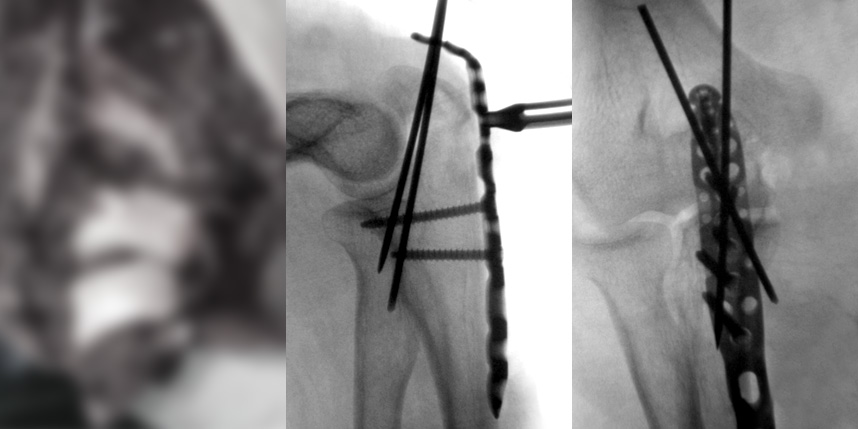

상완골 골절

골절은 정확하게 골절편을 잘 맞추고 고정하는 것이 중요합니다. 특히 관절면을 잘 맞추는 것이 중요합니다.

감탄정형외과는 정확한 초기 진단을 통해 골절 발생일로부터 최대한 빨리 원래의 뼈 상태에 가깝게 원복시키고,